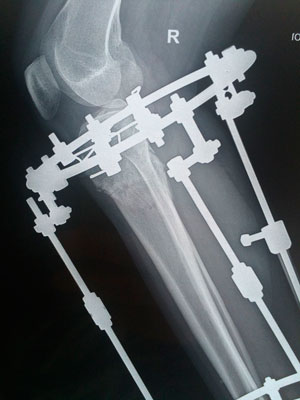

Исходник - 34 года.

Дата операции 29.09.2017г.

Дата снятия аппаратов 27.12.2017г.

Срок лечения 88 дней.

Красотище